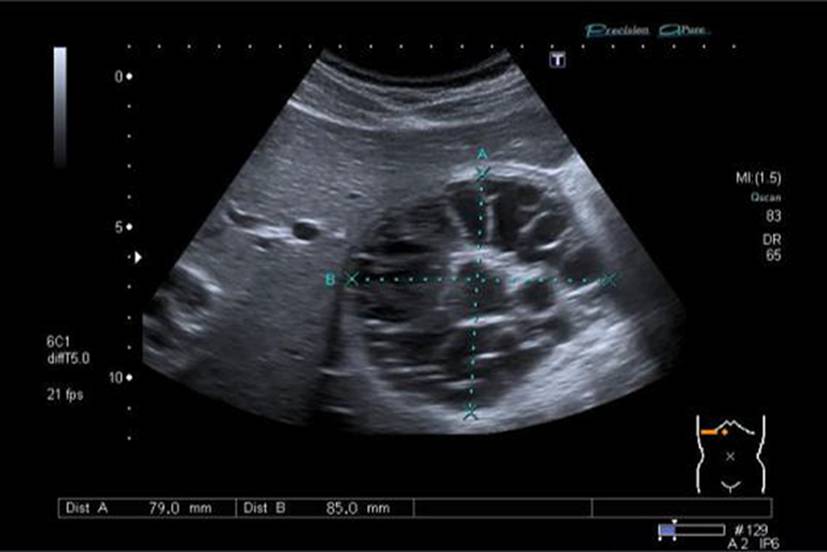

Die alveoläre Echinokokkose (AE) zeigt in der Bildgebung eine breite morphologische Variabilität und kann sowohl zystische als auch solide oder gemischt zystisch-solide Strukturen aufweisen (Abb. 1). Selbst für erfahrene Radiologen ist es oft schwierig, AE-Läsionen von malignen Erkrankungen wie intrahepatischem Cholangiokarzinom oder Lebermetastasen sowie von benignen Veränderungen wie Hämangiomen oder zystischer Echinokokkose zu unterscheiden. Zur Klassifizierung von AE-Läsionen wurden für Ultraschall, CT und MRT verschiedene deskriptive Systeme entwickelt [1315]. Diese haben aktuell vor allem in der Forschung eine Bedeutung. Im Ultraschall erscheint eine AE häufig als avaskulärer, gemischt echogener Tumor mit pseudozystischen oder verkalkten Anteilen, was gelegentlich Hämangiomen oder Metastasen ähneln kann [15]. Ein wichtiger Aspekt in der Bildgebung ist, dass der Nachweis von Verkalkungen nicht als Zeichen einer inaktiven Erkrankung gewertet werden darf [16].

Abb. 1

Verschiedene Präsentationen der alveolären Echinokokkose im Ultraschall. a AE, metastasenähnlich, b AE, hämangiomähnlich, c AE, primär zystisch, d AE, primär solide